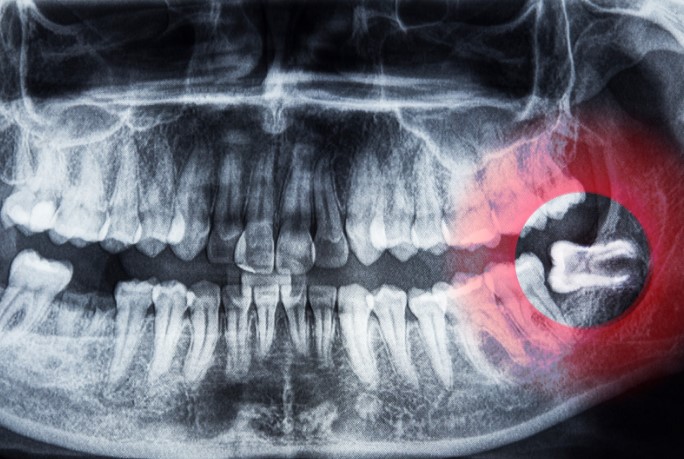

Видалення може ускладнитися через низку причин:

- криві корені,

- наявність кісти,

- руйнування коронки,

- неповне прорізування.